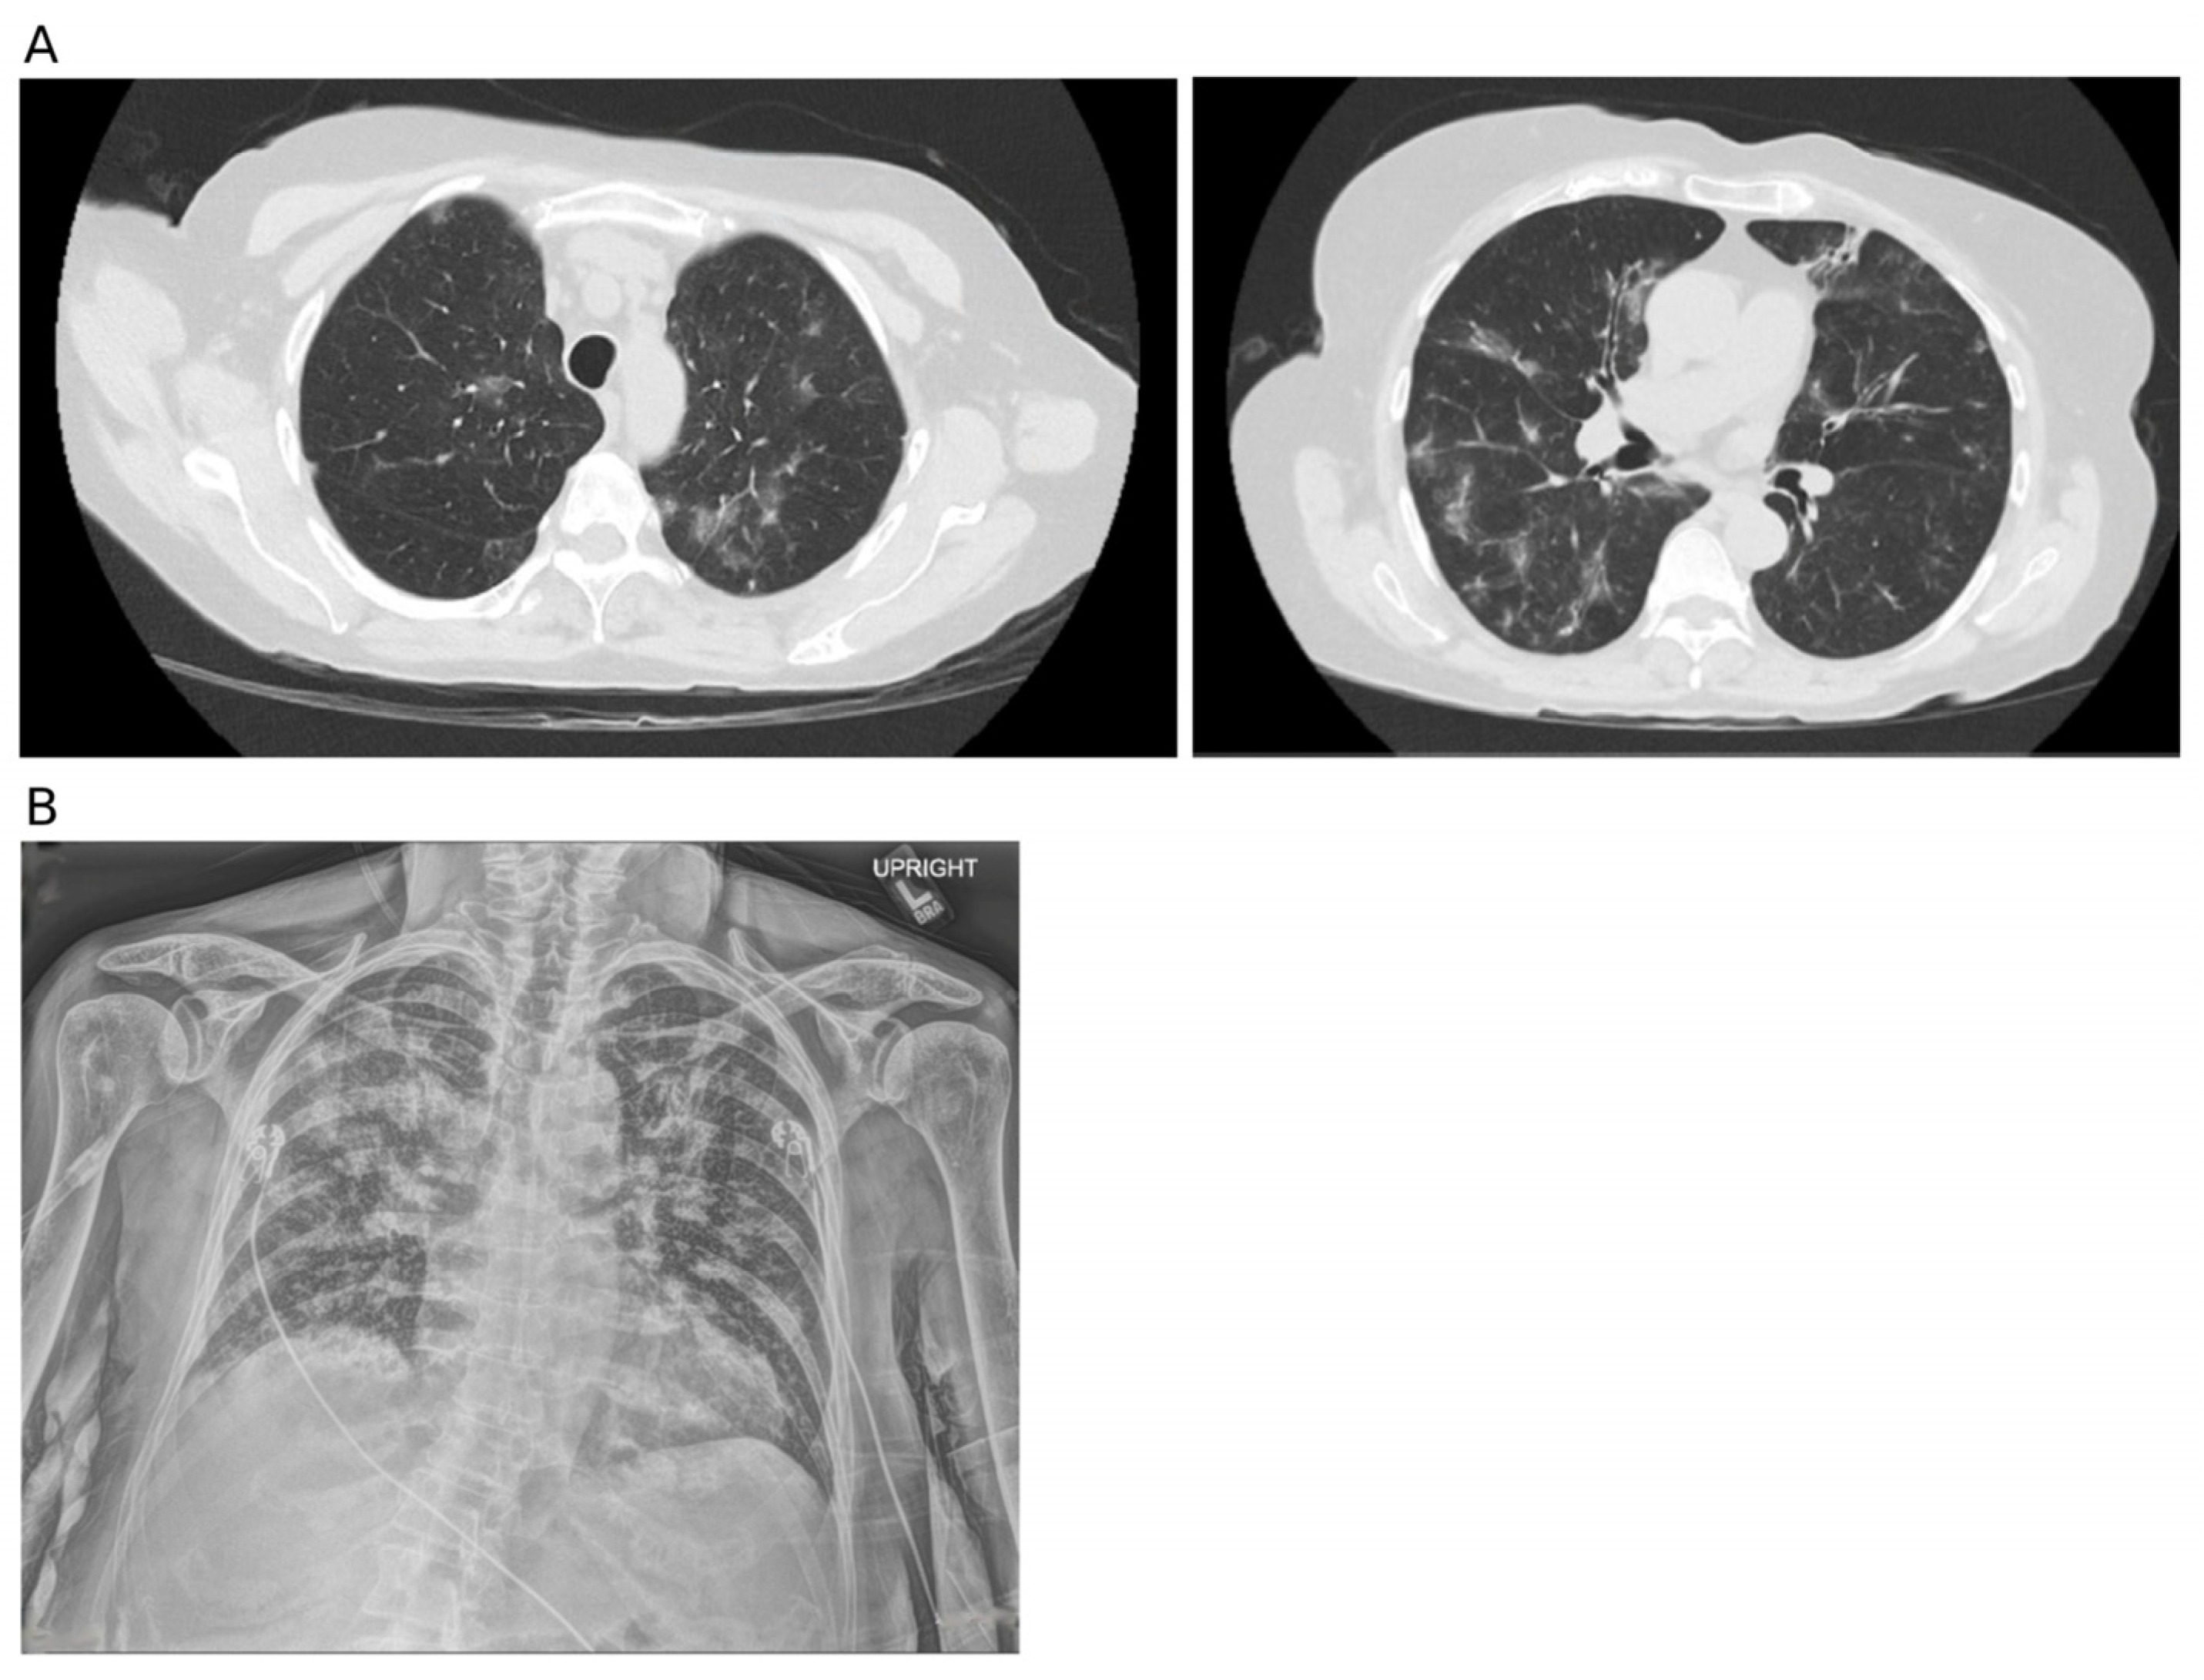

| −8 | Another facility | First CT scan | ||

| 10 | The mold was identified as Verruconis species Second CT scan | Voriconazole 4 mg/kg q12h IV | ||

| Chest CT characteristics | Early signs include: ground-glass infiltration, small nodules | Signs of invasive Aspergillus lung infections include: small nodules, typically granulomas formed by inflammatory infiltration; halo sign: a ground-glass halo around a nodule or mass, indicating hemorrhage around the lesion; cavitation or air crescent sign. | Common CT scan findings include ground-glass infiltrates, multiple opacities, multiple pulmonary nodules, and bronchiectasis. | Greene, R. [19] Park, S.Y. [20] Caillot, D. [21] Greene, R.E. [22] Patterson, T.F. [23] |